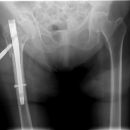

pertrochantäre Femurfraktur